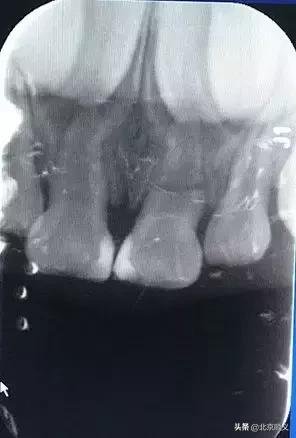

如果是没有完全脱位但是有松动和移位的乳牙,需要拍摄X片,若通过拍摄X光片,发现乳牙外伤已导致明显的根折和移位,建议择期拔除,以防根尖反复感染影响恒牙胚。